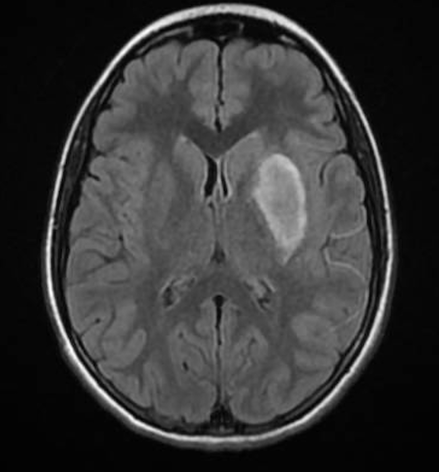

Sulla base dei dati emersi si disponeva il trasferimento presso la Terapia Intensiva Pediatrica del Policlinico Gemelli. All’arrivo la paziente appariva vigile, orientata e collaborante, emodinamicamente stabile, con afasia di produzione, plegia dell’arto superiore destro e paresi dell’arto inferiore destro. Si eseguiva RM encefalo (Figura 1) e si ripeteva angio-TC, con conferma di quadro neuroradiologico compatibile con stroke ischemico da dissezione post-traumatica della carotide interna sinistra (Figura 2) con occlusione tromboembolica del tratto distale di M1, della biforcazione dell’ACM sinistra e di un ramo insulare più distale. Visti il tempo intercorso dall’inizio della sintomatologia, il quadro neuroradiologico e la stabilità del quadro neurologico non vi era indicazione all’esecuzione di trattamento endovascolare o trombolisi sistemica, ma iniziava terapia antiaggregante con acido acetilsalicilico 300 mg/die.

Durante il ricovero in Terapia Intensiva Pediatrica l’emodinamica è rimasta sempre stabile e non si è posta necessità di assistenza respiratoria; dal punto di vista neurologico si evidenziava un iniziale recupero del deficit di forza dell’emilato destro ma persistenza di eloquio ipofonico e ipofluente, con comprensione conservata. Alla RM encefalo di controllo dopo una settimana si documentava stabilità dell’area di sofferenza ischemico-emorragica, assenza di flusso in ACI sinistra, ma pervietà del tratto M1 distale e della biforcazione dell’ACM sinistra. Su indicazione del neurologo si proseguiva terapia antiaggregante e si eseguivano esami ematici per screening trombofilico (PT, aPTT, dosaggio fibrinogeno, D-dimero, antitrombina III), risultati tutti negativi.